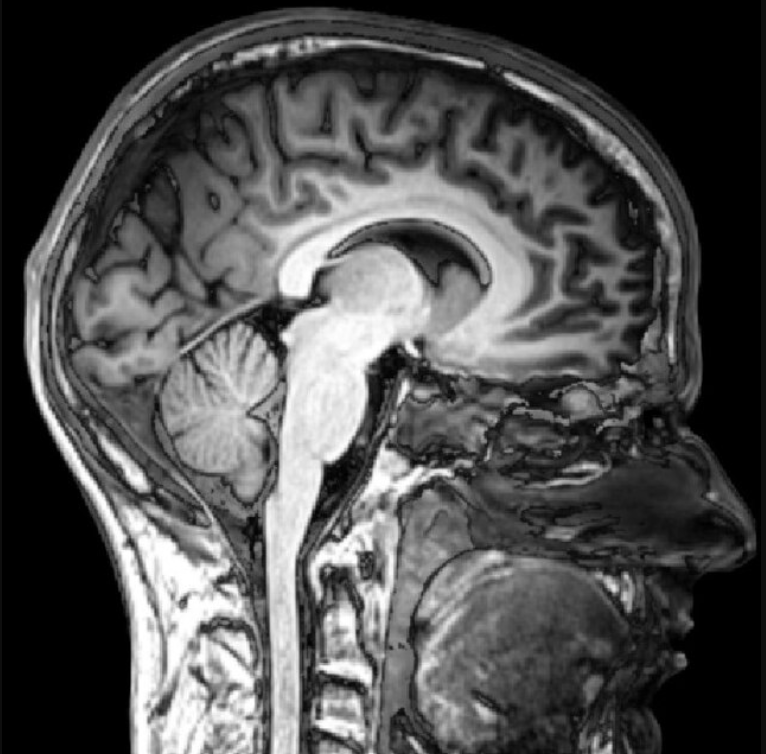

The MRI machine takes images from different angles, and our lab uses three main views of the brain.

• The sagittal view shows vertical slices from the side profile. This view allows researchers to look at the brain from the left side to the right side.

Sagital View